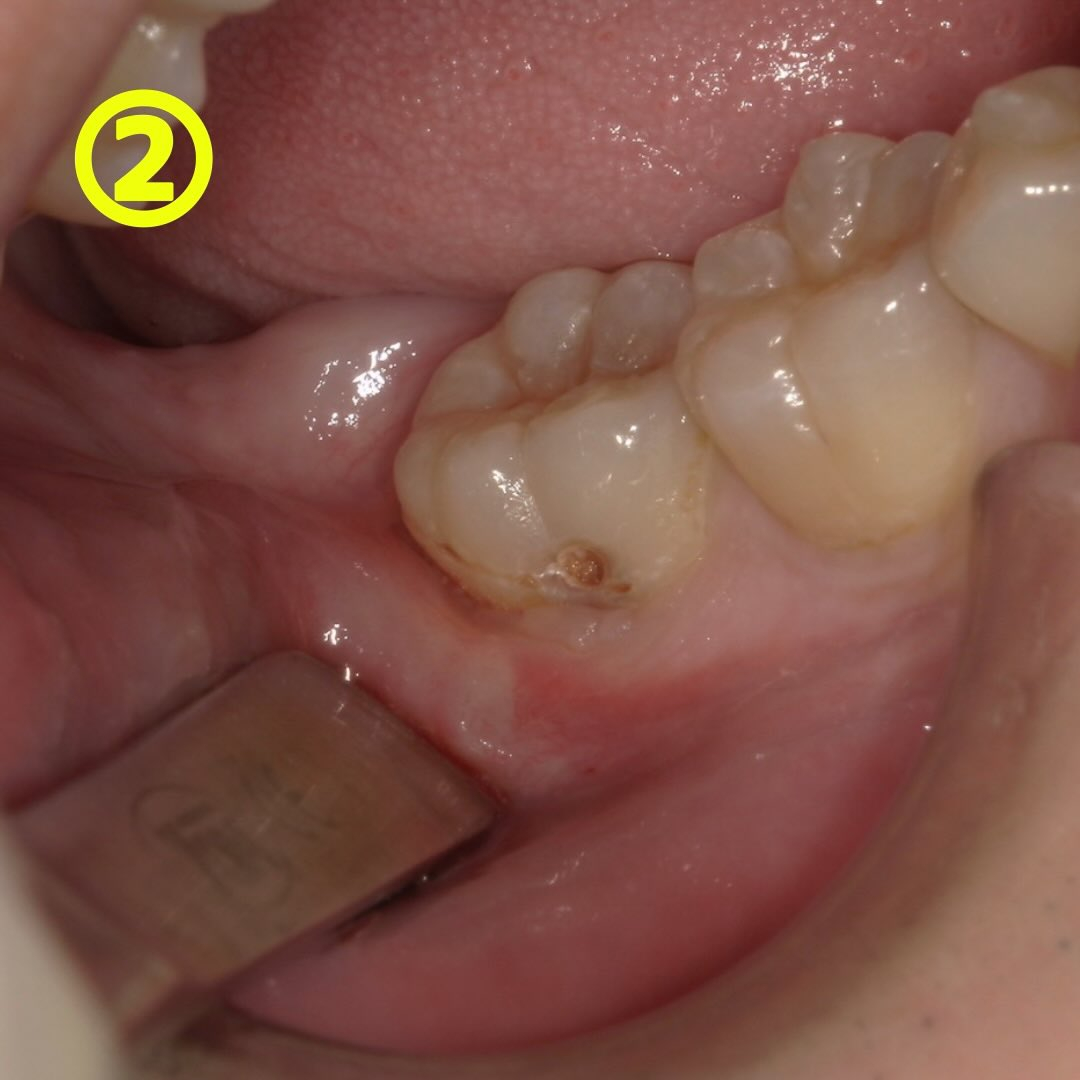

一見小さな窪みの用に見える虫歯ですが(写真①の黄色〇)、削ってみると中が茶色くなっています👀→写真②

②の写真の際に染め出してみました。→写真③